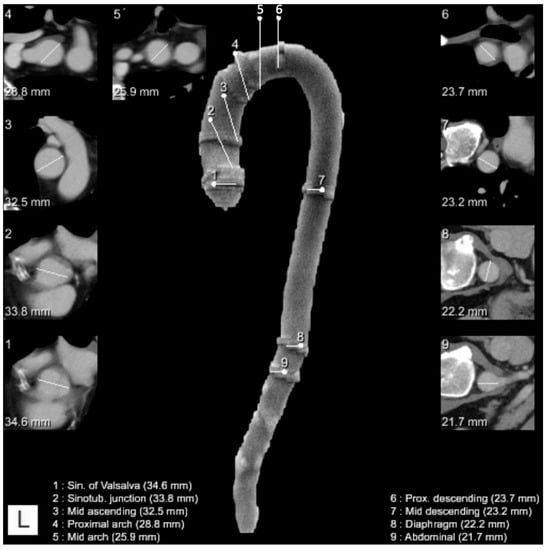

Figure 2.

Example of a reconstruction of the thoracic aorta with location and diameter of the measurements at each dedicated location (legend on the bottom of the image describing the location and the measured diameter). White lines: measurements of the diameter at each dedicated location. In frame images (numbered 1–9 in the top left corner): depiction of the automated diameter measurements in the respective planes perpendicular to the center line.